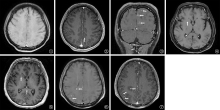

目的: 探讨磁共振三维颅脑容积成像(three-dimension brain volume imaging,3D BRAVO)增强扫描在颅内结核影像诊断中的价值。方法: 收集2021年4月至2024年8月首都医科大学附属北京胸科医院临床确诊及资料完整的122例颅内结核患者作为研究对象。所有患者均进行了结核病相关实验室检查(包括脑脊液检测)、头颅磁共振平扫及增强扫描检查,以及磁共振3D BRAVO增强扫描检查。分析研究对象头颅磁共振常规增强扫描及3D BRAVO增强扫描的影像学特点,并评价磁共振3D BRAVO增强扫描在颅内结核影像诊断中的价值。结果: 患者临床表现存在结核中毒症状和呼吸系统症状(如咳嗽、咳痰、胸痛等)者32例(26.2%,32/122);出现发热、头痛者81例(66.4%,81/122);具有神经系统症状和体征者73例(59.8%,73/122),其中,脑脊液实验室检查常规和生化异常者113例(92.6%,113/122)。所有患者均行腰椎穿刺术检查,颅内压高于180mmH2O(1mmH2O=0.0098kPa)者57例(46.7%,57/122)。122例患者头颅常规磁共振增强扫描:30例(24.6%,30/122)显示为脑膜型,40例(32.8%,40/122)显示为脑实质型,29例(23.8%,29/122)显示为混合型(脑膜及脑实质病变并存),23例(18.9%,23/122)未见颅内结核病变;磁共振3D BRAVO增强扫描:43例(35.2%,43/122)显示为脑膜型,22例(18.0%,22/122)显示为脑实质型,45例(36.9%,45/122)为混合型,12例(9.8%,12/122)未见颅内结核病变。磁共振3D BRAVO增强扫描对颅内结核患者病灶检出率明显高于头颅磁共振常规增强扫描,差异有统计学意义(χ2=9.091,P=0.001);对脑膜结核的检出率明显高于头颅磁共振常规增强扫描,差异有统计学意义(χ2=27.034,P<0.001)。磁共振3D BRAVO增强扫描122例患者中,9例并发脑积水、29例并发脑梗死、10例并发脑神经病变。结论: 磁共振3D BRAVO增强扫描对颅内结核的分型和早期发现具有重要辅助诊断价值。

Objective: To investigate the value of three-dimensional brain volume imaging (3D BRAVO) contrast-enhanced magnetic resonance imaging (MRI) in the imaging diagnosis of intracranial tuberculosis. Methods: A total of 122 patients with intracranial tuberculosis who were clinically diagnosed and had complete data at Beijing Chest Hospital affiliated to Capital Medical University from April 2021 to August 2024 were collected as the research subjects. All patients underwent tuberculosis related laboratory tests (including cerebrospinal fluid testing), cranial MRI plain and enhanced scans, and 3D BRAVO enhanced MRI scans. The imaging characteristics of the study subjects’ skull magnetic resonance conventional enhanced scan and 3D BRAVO enhanced scan were analyzed, and the value of magnetic resonance 3D BRAVO enhanced scan in the imaging diagnosis of intracranial tuberculosis was evaluated. Results: Thirty-two cases (26.2%, 32/122) had clinical manifestations of tuberculosis poisoning and respiratory symptoms (such as cough, sputum, chest pain, etc.); 81 cases (66.4%, 81/122) experienced fever and headache; 73 cases (59.8%, 73/122) had neurological symptoms and signs, among which 113 cases (92.6%, 113/122) had routine and biochemical abnormalities in cerebrospinal fluid laboratory tests. All patients underwent lumbar puncture examination, and 57 cases (46.7%, 57/122) had intracranial pressure higher than 180 mmH2O (1 mmH2O=0.0098 kPa). All patients underwent routine magnetic resonance enhanced scans of their heads: 30 cases (24.6%, 30/122) showed meningeal type; 40 cases (32.8%, 40/122) showed parenchymal type, 29 cases (23.8%, 29/122) showed mixed type (meningeal and parenchymal lesions coexisted), 23 cases (18.9%, 23/122) showed no intracranial tuberculosis; Magnetic resonance 3D BRAVO enhanced scan: 43 cases (35.2%, 43/122) showed meningeal type; 22 cases (18.0%, 22/122) showed cerebral parenchyma type, 45 cases (36.9%, 45/122) showed mixed type, and 12 cases (9.8%, 12/122) showed no intracranial tuberculosis. The detection rate of lesions in intracranial tuberculosis patients by 3D BRAVO enhanced magnetic resonance imaging was significantly higher than that by conventional enhanced head magnetic resonance imaging, and the difference was statistically significant (χ2=9.091, P=0.001); The detection rate of meningeal tuberculosis was significantly higher than that of routine enhanced head magnetic resonance imaging, and the difference was statistically significant (χ2=27.034, P<0.001). Among 122 patients who underwent 3D BRAVO enhanced magnetic resonance imaging, 9 had concurrent hydrocephalus and 29 had concurrent cerebral infarction; 10 cases of concurrent cerebral neuropathy. Conclusion: Magnetic resonance 3D BRAVO enhanced scanning has important auxiliary diagnostic value for the classification and early detection of intracranial tuberculosis.